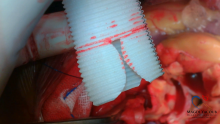

In this video, the authors present the case of a 58-year-old patient who presented with acute aortic dissection (Stanford A). The video demonstrates the surgical technique for the "New Approach for Shaping the Aortic Sinuses and Preserving Dynamism in the Remodeling Operation (2)," commonly referred to as the Yacoub II procedure. Throughout the video, the authors highlight the technical differences between the Yacoub I and Yacoub II procedures.

After nearly four decades of expertise, Professor Magdi Yacoub published novel modifications to the Yacoub remodeling procedure. These enhancements were designed to optimize the physiological impact of the neo-aortic sinuses by maximizing their longitudinal and horizontal curvatures while simultaneously reducing the diameter of the sinotubular junction (STJ) (2).